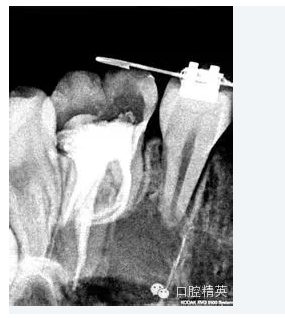

2.根管擴(kuò)大器械可以很明確的告訴我們根管內(nèi)是否具有了應(yīng)用機(jī)用擴(kuò)大針的所必須的平直而通暢的入徑。臨床牙醫(yī)可以通過(guò)手用根管擴(kuò)大器械的形態(tài)確定根管是否較直,平行于牙體長(zhǎng)軸或者彎曲明顯。當(dāng)手用根管擴(kuò)大器械的髓腔部分與牙體長(zhǎng)軸接近平行且能很順利地進(jìn)出根管時(shí),臨床醫(yī)生可以確定此牙的根管系統(tǒng)情況良好,可以直接應(yīng)用機(jī)用擴(kuò)大針;當(dāng)手用根管擴(kuò)大器械的髓腔部分與牙體長(zhǎng)軸有較大角度且進(jìn)出根管較困難時(shí),臨床醫(yī)生可以確定此牙的根管系統(tǒng)必須進(jìn)一步應(yīng)用手用根管擴(kuò)大器械后方可應(yīng)用機(jī)用擴(kuò)大針。為了為機(jī)用擴(kuò)大針的應(yīng)用提供良好的條件,一般情況下可以通過(guò)去除二期牙本質(zhì)、擴(kuò)大根管口來(lái)獲得預(yù)期效果。這一步對(duì)于整個(gè)根管治療過(guò)程都是至關(guān)重要的,可以大大簡(jiǎn)化以后的治療程。 、

5.根管髓腔部分的預(yù)先擴(kuò)大可以幫助牙醫(yī)做出更明確的診斷。預(yù)先擴(kuò)大的根管髓腔部分可以容納較大型號(hào)的金屬根管擴(kuò)大器,X光片顯示更清晰;由于接觸頭更容易的與髓腔牙本質(zhì)接觸,電子根尖定位器的顯示也更明確。

根尖1/3的擴(kuò)大及最后完成

當(dāng)根管的髓腔向2/3的擴(kuò)大完成以后,臨床牙醫(yī)即可順利的進(jìn)行根尖1/3的擴(kuò)大及最后精細(xì)完成。因?yàn)榇蟛糠值难栏鶑澢胺植娑及l(fā)生在該區(qū)域,所以,應(yīng)先應(yīng)用小型的不銹鋼可彎曲的根管擴(kuò)大針對(duì)其進(jìn)行小心而精密的探測(cè),以獲得更詳細(xì)而準(zhǔn)確的診斷資料。